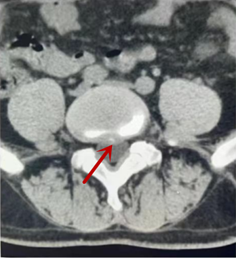

利器二:CT

CT利用X射線對人體檢查部位通過電腦切成若干層掃描,然后把每層的圖像都能顯示出來。CT相對于X光片具有更高的密度分辨力,可直接顯示X線片無法顯示的病變,觀察腰椎有無微小的骨折、骨質(zhì)有無破壞等骨質(zhì)情況、以及腰椎間盤突出、腰椎神經(jīng)根、椎管、椎間小關(guān)節(jié)的情況等。同時還可以通過后處理,重建腰椎矢狀位或冠狀位圖像,形成腰椎的3D圖像,更直觀地觀察病變部位,對腰椎手術(shù)風(fēng)險具有提示作用,對手術(shù)方式的選擇具有指導(dǎo)意義,但是對神經(jīng)、脊髓損傷程度的顯示不如MRI,軟組織的分辨率仍有一定限制,對椎管內(nèi)病變顯示欠佳,且有一定的輻射。

箭頭提示椎間盤突出

從左向右依次為CT矢狀位重建圖像、三維重建圖像、軸位掃描圖像,箭頭提示腰1椎體爆裂性骨折